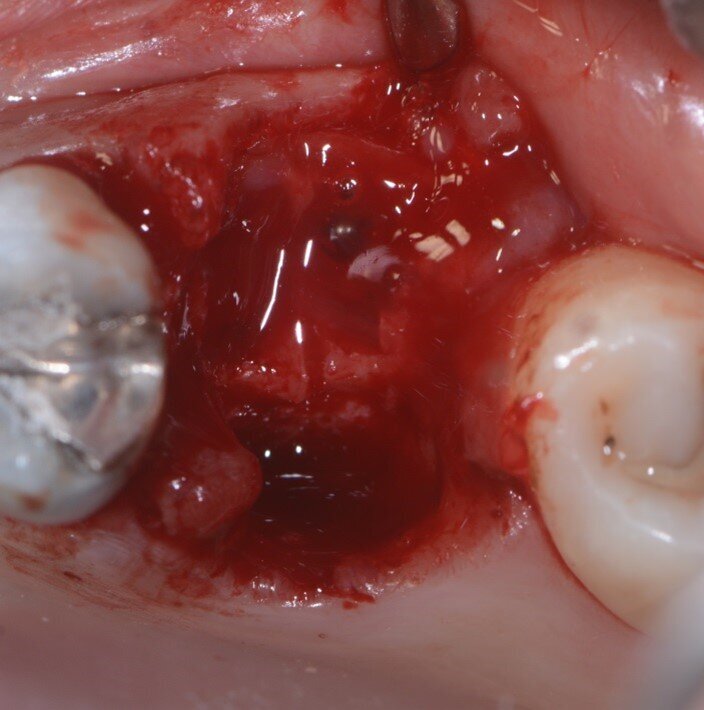

È stata eseguita una CBCT preoperatoria (Figg. 2a, 2b). La paziente, una donna di 52 anni in buona salute, ha iniziato la terapia antibiotica il giorno prima dell’estrazione con 2 gr. Amoxicillina e Acido Clavulanico. Dopo l’anestesia locale, è stata eseguita un’estrazione atraumatica cercando di non danneggiare le corticali ossee. L’alveolo è stato accuratamente pulito e risciacquato con acqua ossigenata e clorexidina 0,2% (Fig. 3). È stata praticata un’incisione intrasulculare sull’aspetto vestibolare dell’alveolo estrattivo, estendendosi al centro dei denti adiacenti. Un lembo a tutto spessore è stato sollevato ed il periostio staccato con micro-scollatori ha permesso di creare una busta per la lamina corticale (Fig. 4). La lamina corticale soft da 0,5 mm è stata prima idratata per cinque minuti in soluzione sterile e poi tagliata nella forma desiderata, tra 8 e 10 mm di altezza e con un’estensione che copre i margini mesiali e distali dell’alveolo estrattivo. La lamina corticale può essere facilmente inserita nel sito ed eventualmente ritagliata fino ad ottenerne un perfetto adattamento. I bordi devono essere rifiniti con angoli arrotondati per ridurre il rischio di perforazione e/o deiescenze sul versante vestibolare. La colla di fibrina umana (Tisseel, Baxter) è stata diluita al 10% mediante 0,9 ml di acqua bidistillata. Sulla lamina corticale sono state applicate due o tre gocce di colla, dopo di che la lamina è stata poi schiacciata con una gentile pressione digitale per adattarsi alla posizione predefinita (Fig. 5). Il lato palatale dell’alveolo è stato invece lasciato guarire per prima intenzione. Una spugna di collagene (Condress, Smith & Nephew) è stata inserita all’interno dell’alveolo per stabilizzare il coagulo ed è stata posizionata una sutura incrociata (4-0 punti di sutura in ptfe) per mantenere la spugna in posizione, le papille sono state invece suturate con due suture a fionda7 (Fig. 6). Quattro mesi dopo l’estrazione, prima di inserire l’impianto, è stata eseguita una CBCT post-operatoria per valutare la guarigione del sito operato.

Fig. 6 - Spugna di collagene e suture.